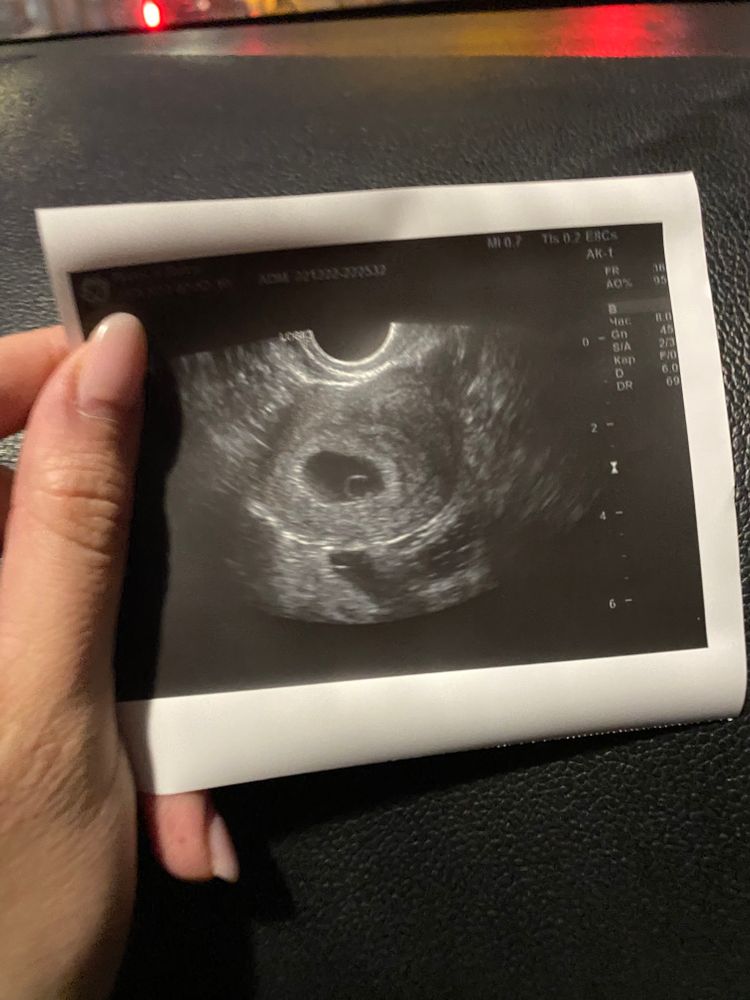

34дпп или 7 недель беременности

2 января делаю узи у своего ре- все отлично, бусинка растет, сердечко активно бьется, отслойки нет, активно начинает формироваться плацента)

сейчас уже человечище)